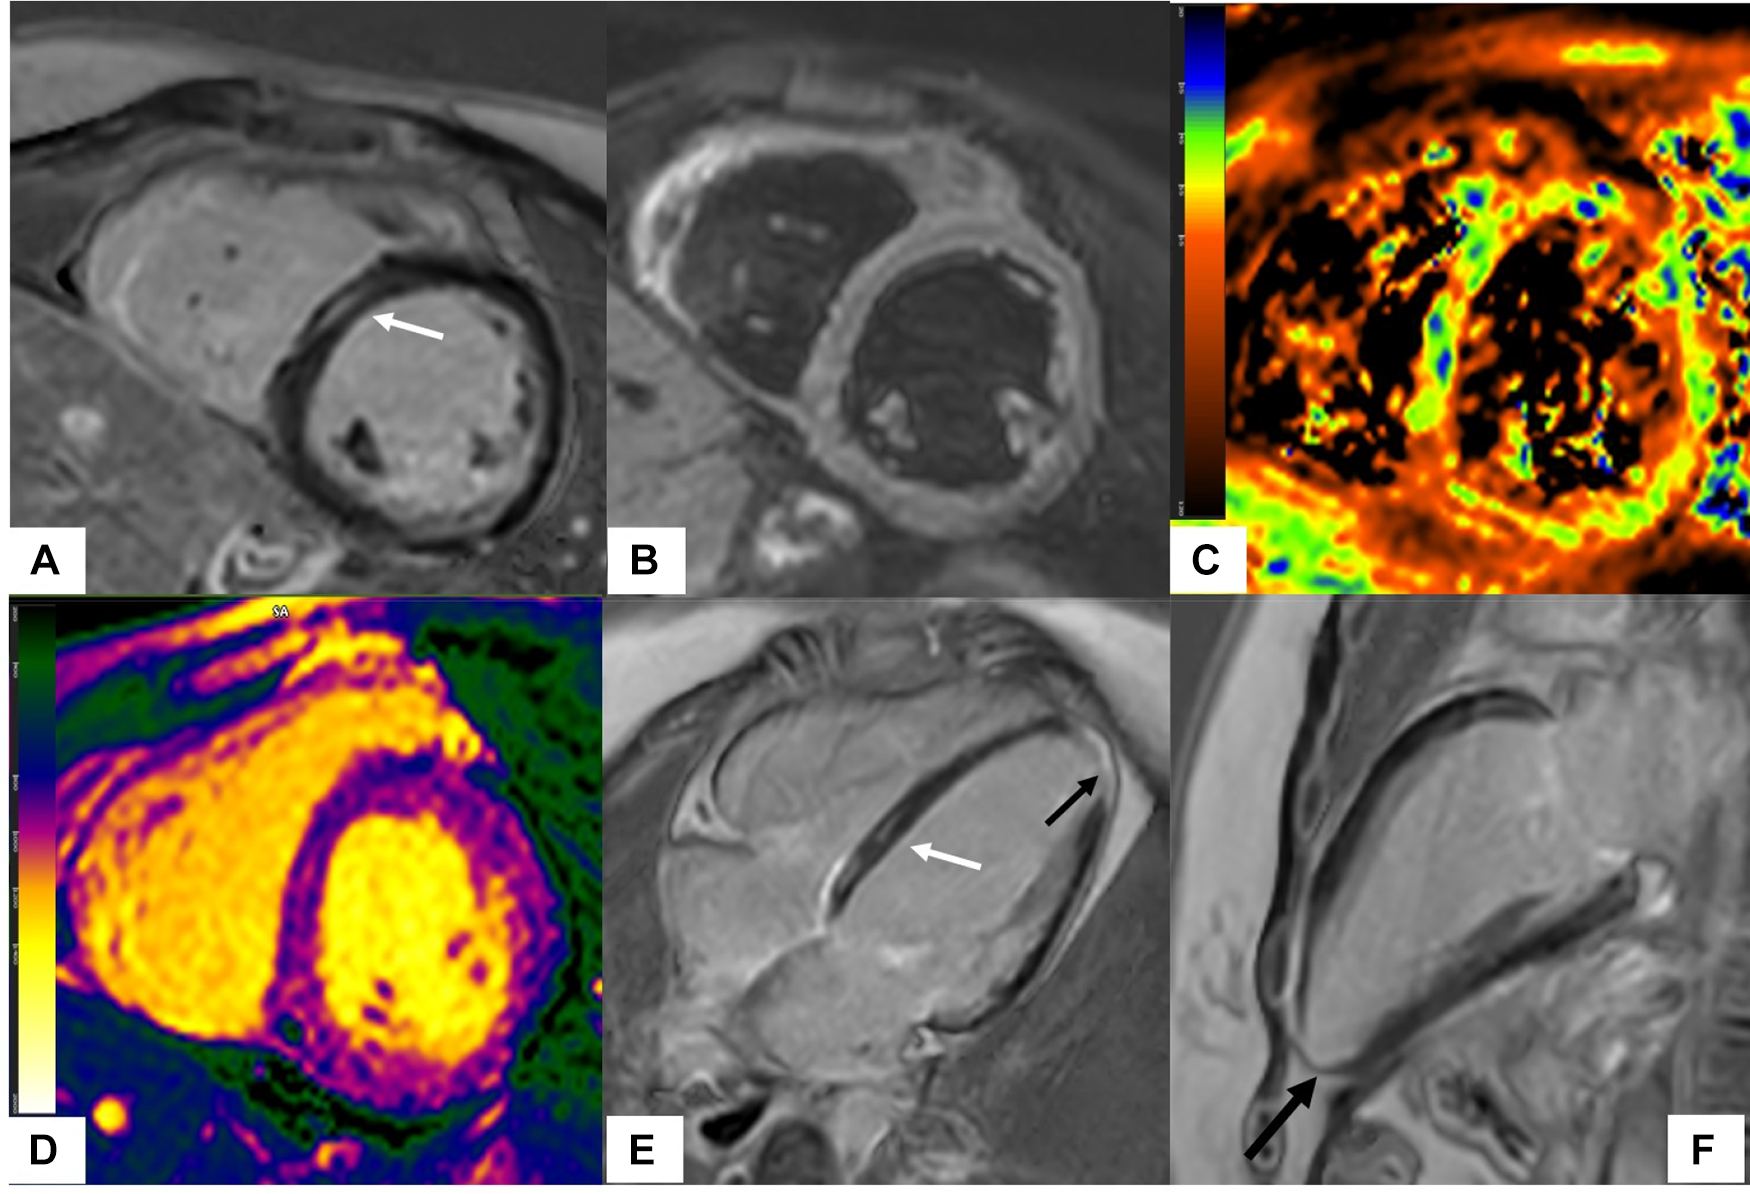

Figure 2

Scleroderma with mixed ischemic and non-ischemic cardiomyopathy on CMR. 20-year-old female with diffuse systemic sclerosis, ANA + anti Scl70 + with interstitial lung disease. Patient had occasional palpitations, ventricular tachycardia (VT) and premature ventricular contractions (PVC) burden of 13.2% on Holter monitoring. Cardiac MR (CMR) revealed normal size LV with low normal LV systolic function with left ventricular ejection fraction (LVEF) 54%, moderately dilated RV with moderately reduced right ventricular ejection fraction (RVEF) of 39%. On short-axis and 4-chamber late gadolinium enhancement phase-sensitive inversion recovery (LGE PSIR), mid myocardial late gadolinium enhancement was seen in the septum in a non-coronary distribution (A,E white arrows) without increased signal on short-axis T2w BB FS images (B), normal T2 values on T2 color map (C) and normal native T1 value on native T1 color map (D) These findings were suggestive of chronic myocardial fibrosis related to scleroderma involvement (42). Transmural LGE with akinetic apical anterior wall and apex was seen on the 4-chamber and 2-chamber views (black arrows E,F) suggestive of chronic microvascular injury and myocardial infarction in the absence of epicardial disease. Overall, findings of mixed ischemic and non-ischemic etiology were likely related to systemic sclerosis.